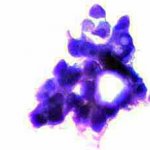

Κατόπιν αυτού, παρακέντηση λεπτής βελόνης κάτω από υπερηχογραφικό έλεγχο και άμεση χρώση παρασκευάσματος κατά Papanicolaou. Κυτταρολογικώς χαρακτηριστικές εικόνες νεοπλασίας.